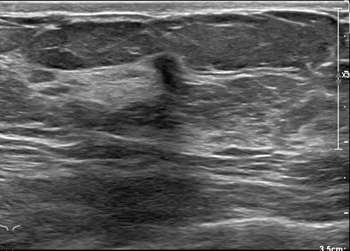

Case: Invasive Lobular Carcinoma Figure 2

Diagnostic imaging of the same patient revealed an area of architectural distortion in the right breast at 9 o’clock, upper outer quadrant at middle depth. Ultrasound revealed a corresponding hypoechoic irregular mass with angular margins and posterior shadowing. Ultrasound guided biopsy was recommended which revealed invasive lobular carcinoma. MRI was recommended for further evaluation of multicentric, multifocal disease.